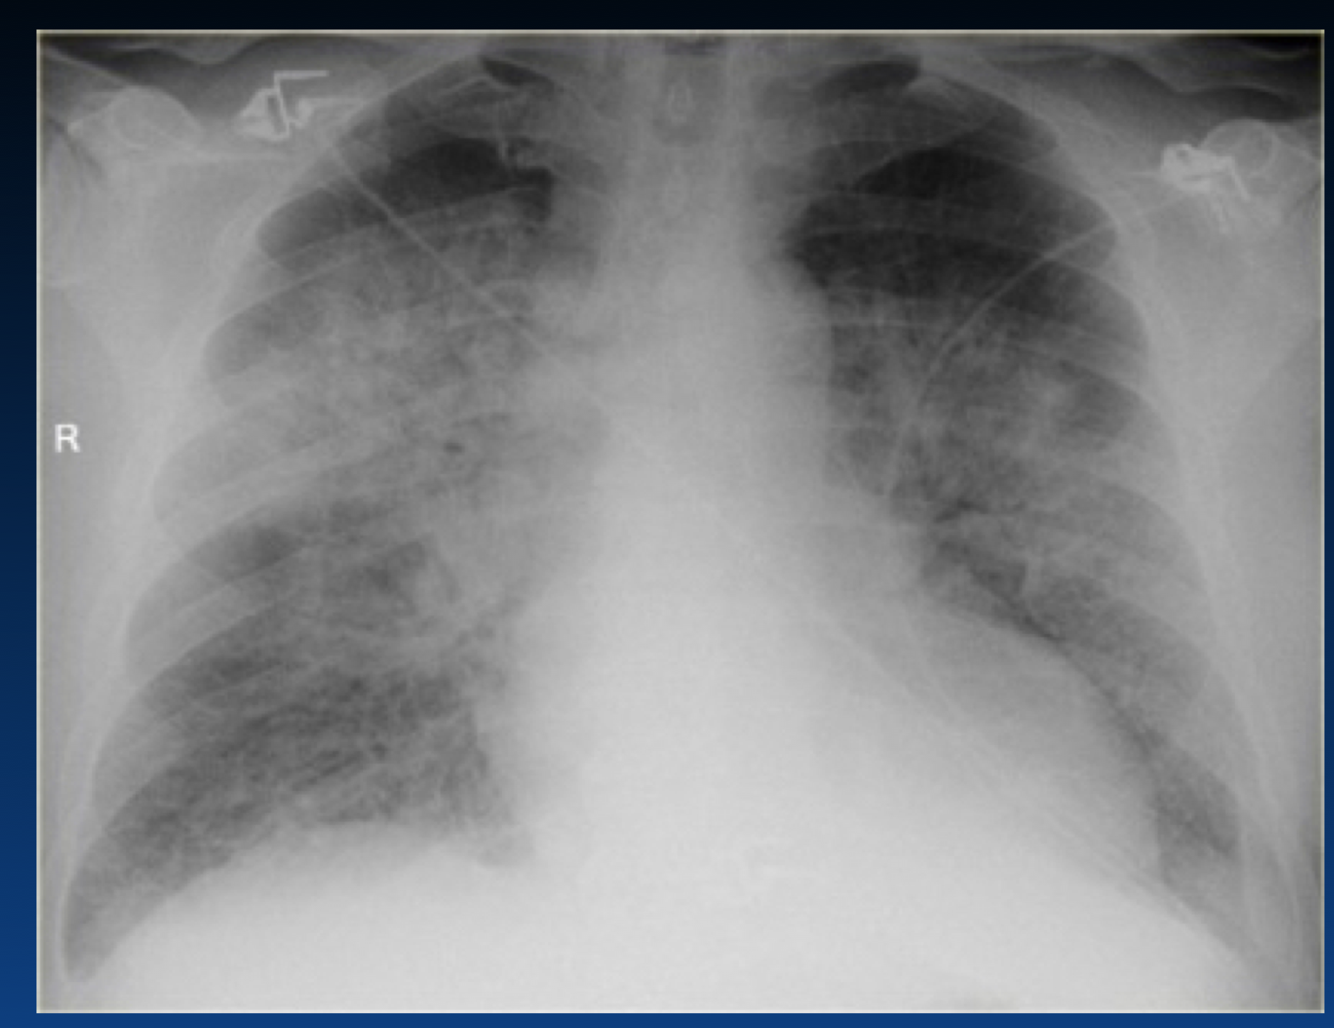

What occurs in this stage of CHF?